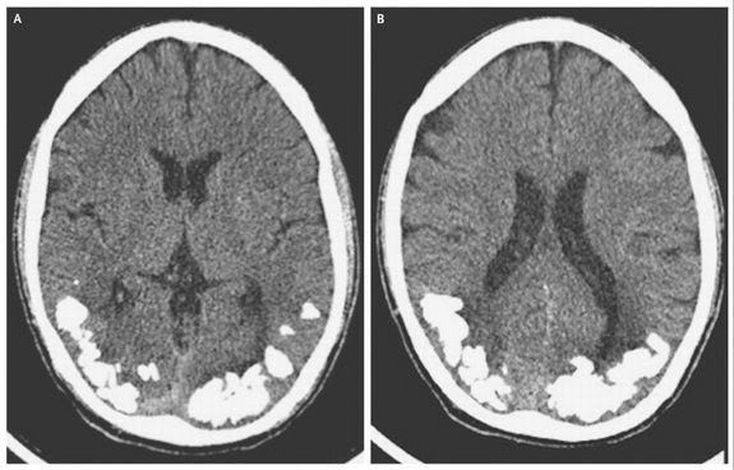

For 10 years a young man in Brazil had been suffering from throbbing headaches and vision problems. On close examination, it turned out there were small stone-like calcium deposits in his brain. This was apparently an extreme complication brought about by Celiac disease, an autoimmune disorder that over time affected the lining of the small intestine reduced the body's ability to absorb nutrients. It is unclear how exactly celiac disease resulted in calcification in the brain, but researchers said it is possible that the patient's lowered ability to absorb iron may have had a role.

This requires surgery, the Ca2+ deposits are stone like and therefore can't be removed by the body. A gluten free diet will stop the build up but it will forever be there without surgical intervention. The headaches are from increased cranial pressure, they will also cause developmental difficulties if not removed. This may include normal hormonal activity when reaching puberty and everyday hormonal release. Also because it is in the occipital lobe, I estimate that over time it may cause visual perception issues.